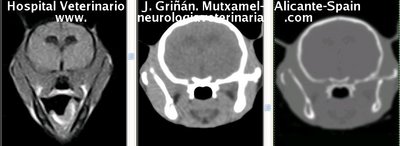

Se muestran cortes transversales de Resonancia Magnética (imagen a la izqda del lector), TC contrastado para tejidos blandos (imagen del centro) y TC contrastado para tejidos duros (imagen de la derecha del lector).

Nótese como la Resonancia supera al TC en el contraste de tejidos blandos (encéfalo y médula espinal) y en el de líquidos (ojo y líquido cefalorraquídeo), mientras que el TC supera a la resonancia en el contraste de tejidos duros (hueso) y aire (senos, cavidad nasal y bullas)

Cortes a nivel de los bulbos olfatorios